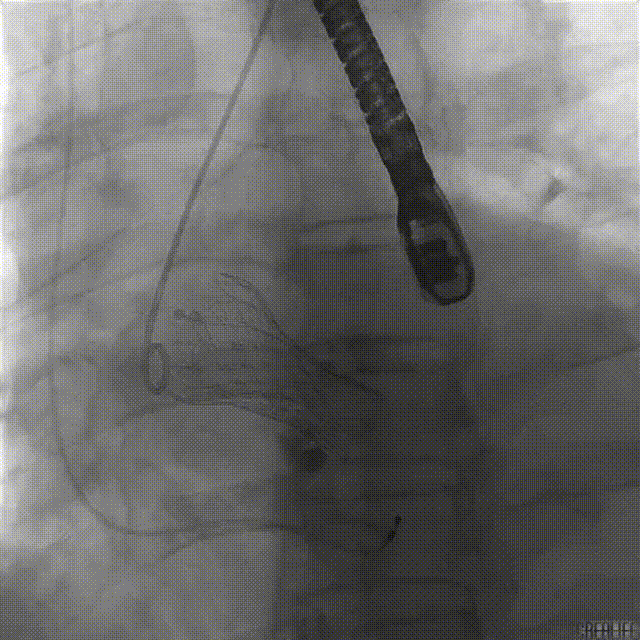

球囊预扩张

递送到达释放位